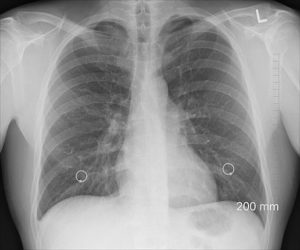

According to studies, Cannabis does not impair lung function and may lead to increased lung capacity. Unlike the use of cigarettes, when you smoke Cannabis, your lungs are not affected. Furthermore, research has established that tobacco smokers suffered from lung function over time, but marijuana users showed no harm other than increased lung capacity. Also, it may aid in reversing tobacco’s carcinogenic effects.